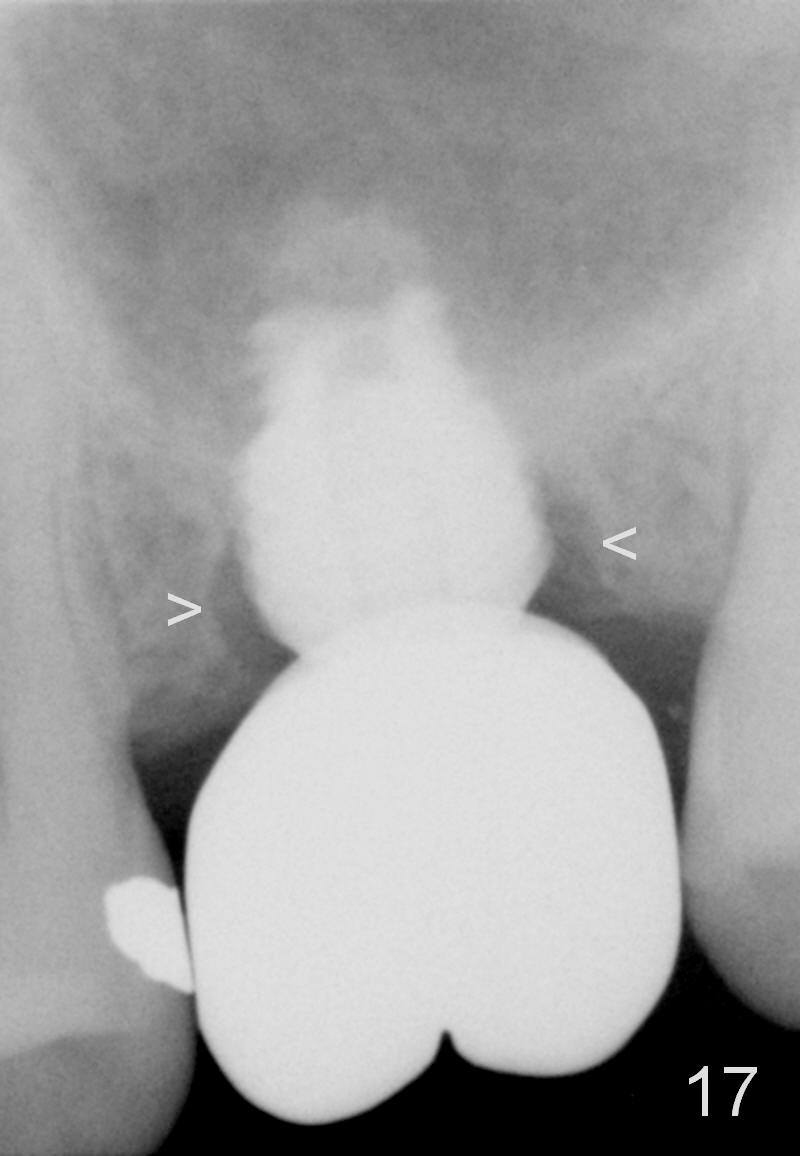

A 45-year-old man has lost the tooth #14 for a while (Fig.1); bone height is 5.4 mm. An extra wide and short implant is planned. Torus palatinus is large, suggesting that bone density should be high. A 6 mm tissue punch is chosen, but it is placed more palatal. If it were placed in the middle of the ridge, there would be no buccal keratinized gingiva (incision may avoid this issue). Additionally, the buccal portion of punch is made incomplete so that there is pedicle on the buccal side when the flap is raised (Fig.4,8: F). It is expected that the excess portion of keratinized tissue will form thick gingiva buccally. Osteotomy proves that bone is dense (Fig.2 (4.5x11 mm tap). Typical sinus lift is finished with placement of 6.4x6 mm (extra wide) bone-level implant (Fig.3, >55 Ncm). Following further torque, Fig.4 shows that the implant (I) is sub-gingival (<). Bitewings are taken to confirm that the implant plateau is at the crestal level (Fig.5,6 ^). PA shows sinus lift (Fig.7 *). The lingual aspect of the implant and healing abutment (H) is further bone grafted and covered by collagen dressing (Fig.8 *). The wound is protected with perio dressing. When the latter dislodges 7 days postop, the collagen dressing and bone graft are lost as well (Fig.10), while the buccal flap remains vital (Fig.9). The lingual exposed plateau should be able to heal normal. The collagen dressing should have been fixed in place by suture or as simple as a dental floss. There is mild nasal hemorrhage 1-2 days postop, possibly related to sinus membrane perforation and inability of Collagen Dressing to cover the perforation and contain the bone graft. When the patient returns for #9 implant placement in 3 weeks postop, the buccal flap reduces in size (Fig.11 *), while the palatal wound has healed with minimal exposure of the implant (Fig.12). Sinus graft remains in place 3 months postop (Fig.13); the buccal flap appears to have incorporated into a part of the gingiva (Fig.14). The bone density of the sinus lift appears to increase 10 days later when an abutment is placed (Fig.15 *). Although oral hygiene is pristine, there is apparent crestal bone resorption 12 months (Fig.16) and 20 months (Fig.17) post cementation, probably due to unfavorable crown/implant ratio and bruxism as well as pre-implantation bone loss (Fig.18,19). In contrast, an immediate implant in the same patient avoids pre- or post-implantation bone loss. In fact both the soft (Fig.20) and hard (Fig.21) tissues remain healthy 2 years 8 months post cementation. The sinus lift remains 3 years 8 months post cementation (Fig.22), while the crestal bone loss persists. The patients keeps complains of food impaction distal associated with bad smell 4 years 1 month post cementation. In fact the distal proximal contact is within normal limit. The bad smell is probably due to crestal bone loss (Fig.23 (pan), 24 (CT) *) and periimplantitis. Bone graft, PRF and Cytoplast membrane will be needed and fixed in place with long healing screw. When the patient returns for crown redo, he also reveals floss related gingival hemorrhage. There is pain associated with palatal sulcus probing with light gingiva erythema. Review of CT coronal section shows possible palatal (Fig.25 P) bone loss (*).